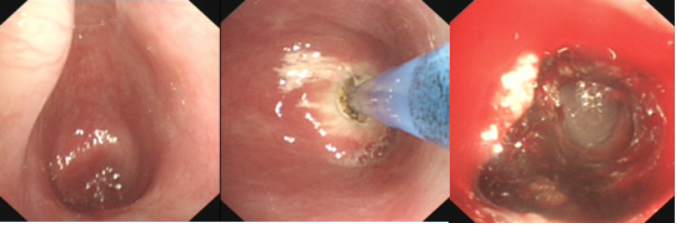

3. 中心气道阻塞的快速解除

床旁支气管镜可以快速解除中心气道阻塞,适用于:①气道内异物,包括分泌物、积血以及其他异物(图1);②良性病变。例如感染、良性肿瘤或增生、气道支撑结构的破坏等(图2);③恶性病变,例如气道内肿瘤组织堵塞、气道壁浸润以及管腔外的压迫(图3)

图3  食管癌侵犯气管致大气道狭窄—覆膜支架植入

病例5急诊处理恶性气道肿瘤

患者,男性,70岁,食管鳞癌侵犯左主支气管,Ⅰ型呼吸衰竭。端坐呼吸,高流量吸氧100%,PaO2 31 mmHg,急诊经鼻气管插管。影像学可见左主支气管非常狭窄。

患者右肺功能欠佳,左主支气管堵塞后出现呼吸困难及窒息。患者当时有创呼吸机辅助通气,气管插管型号为7.5号,无法同时完成气管镜和球囊扩张。所以在清理完肿瘤组织后,将球囊导管从气管插管放到了病变部位,气管镜从气管壁与气管插管之间的缝隙进去。这样就可以在气管镜下进行球囊扩张(图18)。扩张后,患者氧合状态明显改善。

图18  床旁取瘤+球囊扩张